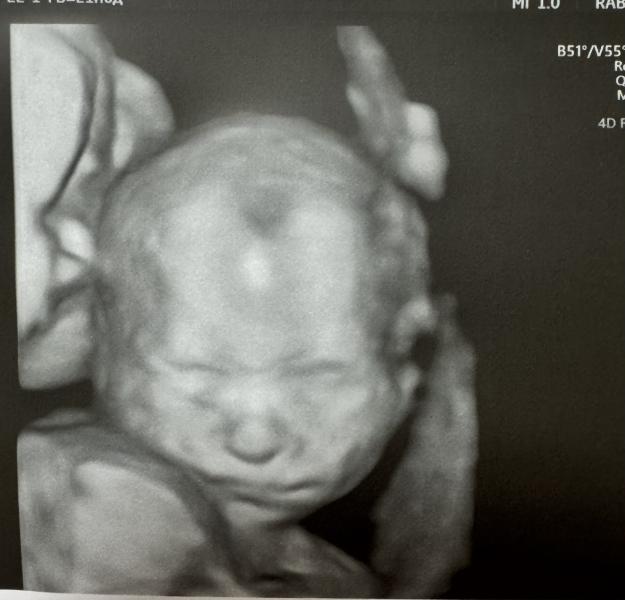

Дал пофоткать личико😍

Ну прям милота….🩵